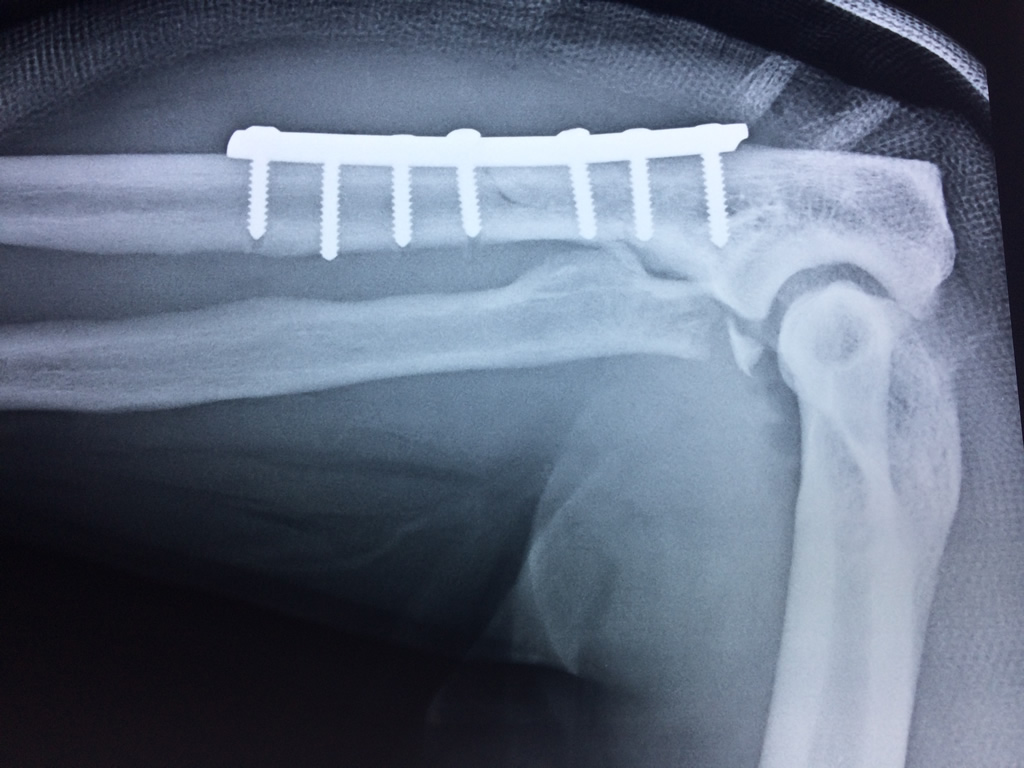

Cirugías de Peroné y Tibia